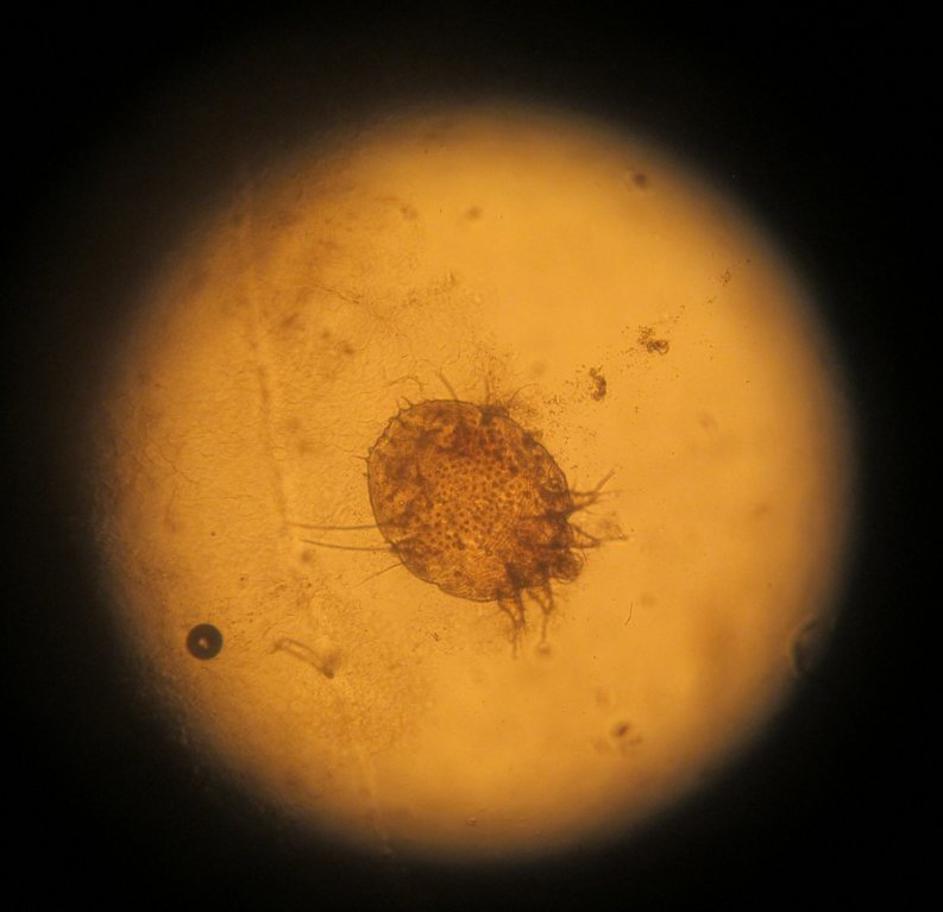

V slovenski šoli so se pojavile garje

Garje Profimedia Garje